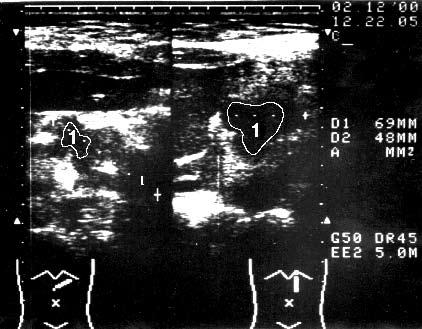

Первым этапом диагностической программы, направленной на выявление опухоли ПЖ и определение ее распространенности, является ультразвуковое исследование (УЗИ). Характерными признаками РПЖ, по данным УЗИ, являются локальное увеличение размеров органа, наличие опухолеподобного гипоэхогенного образования, бугристые контуры ПЖ в области опухоли (рис. 98).

Рис. 98. Ультразвуковое исследование. Рак головки ПЖ. На снимке видна гипоэхогенная бугристая раковая опухоль 5x4 см (1)